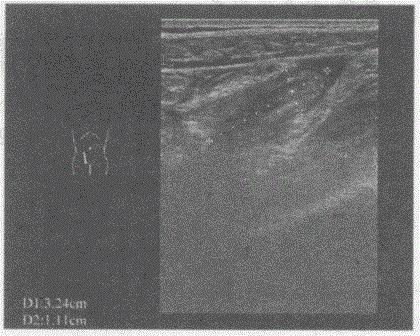

问题 临床资料:女,46岁,自述转移性右下腹痛3天,加重1天。 临床物理检查:右下腹麦氏点压痛、反跳痛。 化验检查:血常规白细胞12.1×10/L,中性粒细胞0.87。 超声综合描述:右下腹可见3.2cm×1.1cm腊肠样管状低回声区,内回声不均,可见0.7cm×0.4cm强回声光团,后伴声影,管状低回声区与回盲部相连,动态观察内未见蠕动。右髂窝可见无回声区,深度1.7cm。 {图2} 超声提示: